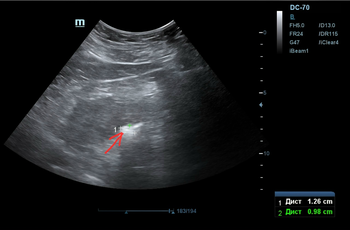

Делаем УЗИ почек (фото 3 — 5) — по центру левой почки подозрение на твёрдый камень, будто состоящий ~ из трёх слившихся фрагментов.

Фото 5 — УЗИ почки

Но он совершенно не беспокоит, и пациент оперативное лечение пока не рассматривает.